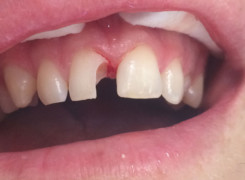

Pan Kamil zgłosił się do gabinetu po wypadku rowerowym w wyniku którego wybił ząb – lewą górną jedynkę. W takiej sytuacji została podjęta decyzja o implantacji natychmiastowej oraz zapatrzeniu pacjenta na czas integracji wszczepu w uzupełnienie tymczasowe.

Poniżej przebieg odbudowy protetycznej.